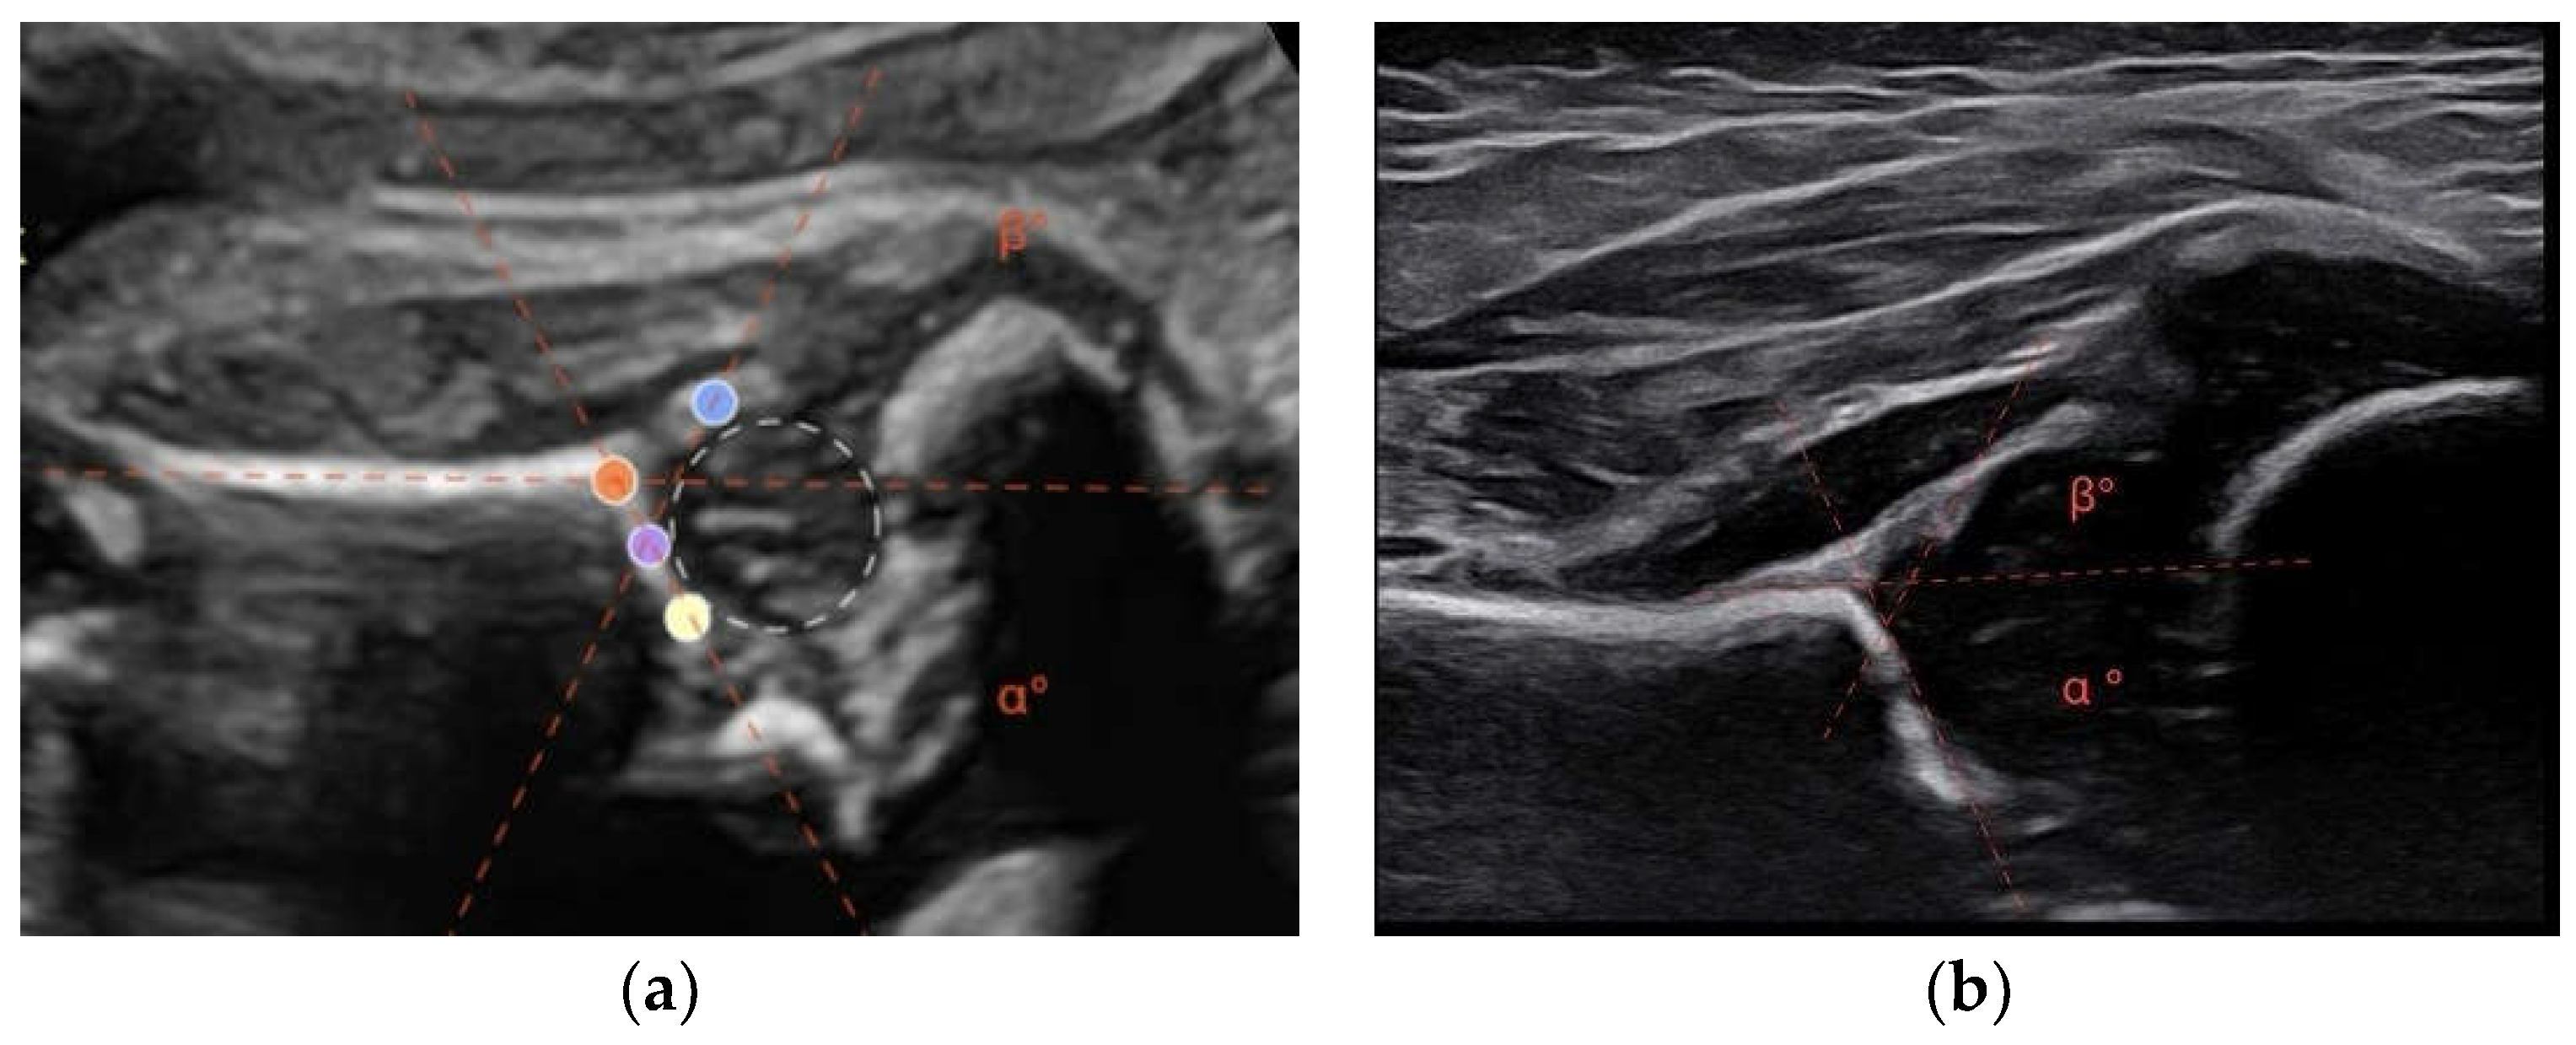

A modified Graf method was performed. This involves acquiring a lateral scan of the newborn’s hip. Similarly, to the Graf method for infants, the alpha angle has been defined as the angle formed between a line tangent to the iliac wing and a line tangent to the bony roof. The angle is formed by the line tangent to the iliac wing and a line tangent to the cartilaginous roof [9,11] (Figure 1).

Figure 1. (a) During the ultrasonographic examination of a 34-week-old fetus, the hip near the maternal abdominal wall was visualized. The acetabular roof (orange), the turning point (purple), the lower edge of ossified ilium (yellow), the labrum (blue). The angles alpha and beta are determined by the intersection of the lines connecting the specified reference points. In this case, the alpha angle measures 61°, while the beta angle measures 64°; (b) The same patient, in the postnatal ultrasound at 6 weeks of age, shows an alpha angle of 65° and a beta angle of 60°.